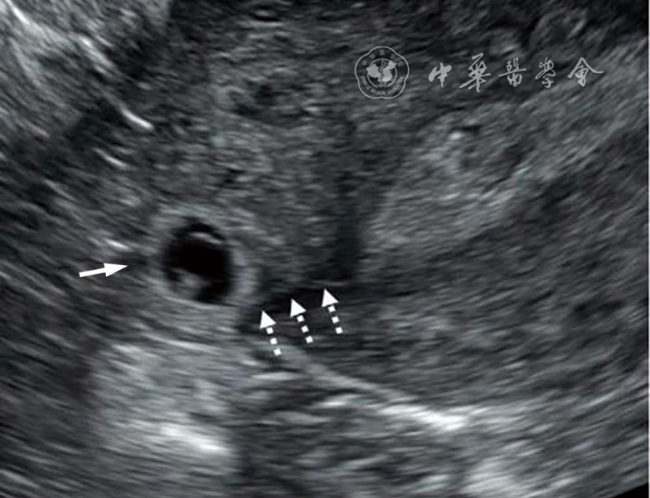

2.宫内妊娠的偏心着床(图2):指受精卵偏心着床于结构正常的子宫。正常妊娠的着床部位常靠近子宫中线,也偶可偏向左右侧,即偏心着床;此时,超声报告应提示为“宫内妊娠”或描述为“妊娠囊偏心着床但完全被子宫内膜包绕”,结论为“宫内妊娠”。该专家共识明确提出了应避免继续使用既往常用的‘宫角妊娠’‘宫角部妊娠’术语表述。

图2 宫内妊娠的偏心着床超声图像,妊娠囊位于偏心位置,但完全被子宫内膜包绕。图a为36岁孕妇(孕5周4天)经阴道超声横切面灰阶超声图,显示一偏离中线靠近左侧的妊娠囊(箭头所示)内含卵黄囊及胚胎。妊娠囊完全被子宫内膜包绕,可直接报告为“宫内妊娠”;也可补充描述为“妊娠囊偏心着床但完全被子宫内膜包绕”,但超声仍提示为“宫内妊娠”,以免与输卵管间质部异位妊娠混淆,避免使用‘宫角妊娠’或‘宫角部妊娠’等术语。图b为三维超声冠状面重建图,有助于确认妊娠囊位于子宫内膜内(图2译自参考文献[1])

考虑该专家共识对既往这一易混淆的临床问题提出明确的重新定义,是因为既往很长一段时间使用的‘宫角妊娠’,实际包含了“宫内妊娠的偏心着床”及“输卵管间质部异位妊娠”两种情况,短期超声随访或三维冠状面重建对两者的鉴别诊断较有帮助。